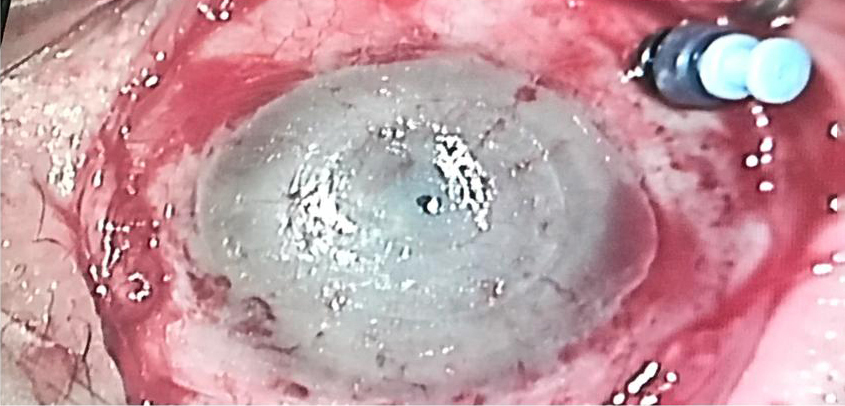

Source: Gilad Litvin, MD

The CorNeat KPro is described on the companyโs website as a โpatented synthetic cornea utilizing advanced cell technology to integrate artificial optics within resident ocular tissue. It is produced using nanoscale chemical engineering, which stimulates cellular growth.โ The CorNeat KPro is designed to integrate under the conjunctiva. Surgically, the CorNeat KPro implantation procedure is designed to reduce the time of โopen sky.โ

Irit Bahar, MD, MHA, who performed the first-in-human CorNeat KPro procedure in January 2021, said the surgical sophistication needed for most KPro procedures and the high rate of complications, due to the procedure or materials, motivated creation of the CorNeat KPro. Prof. Bahar said the first patient who received the CorNeat KPro has been having weekly follow-up with the results exceeding expectations thus far.